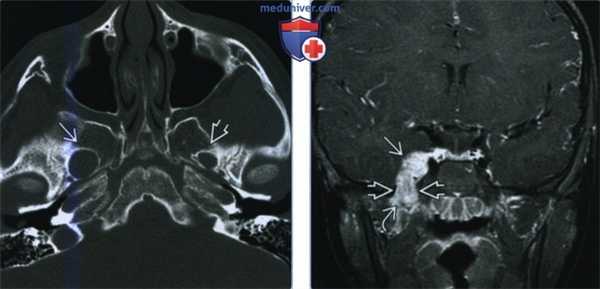

(Слева) На аксиальной КТ с КУ в жевательном пространстве справа визуализируется злокачественная фиброзная гистиоцитома нижней челюсти в виде минимально контрастирующегося солидного объемного образования, разрушающего ветвь и тело нижней челюсти. Жевательное пространство является известным местом возникновения сарком глубоких областей ли ца.

(Справа) На аксиальной КТ с КУ у этого же пациента визуализируется опухоль в жевательном пространстве справа, приводящая к обширной деструкции нижней челюсти. Обратите внимание на асимметрию лица на стороне поражения.